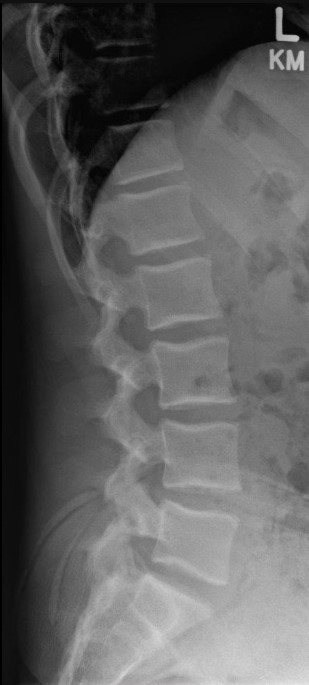

Normal Images Cervical Spine Lateral Xray Cervical Spine CT Cervical Spine MRI Sagittal Cervical Spine MRI Axial Lumbar Spine AP Xray Lumbar Spine Lateral Xray Lumbar Spine CT sagittal Lumbar Spine MRI sagittal Lumbar Spine MRI axial